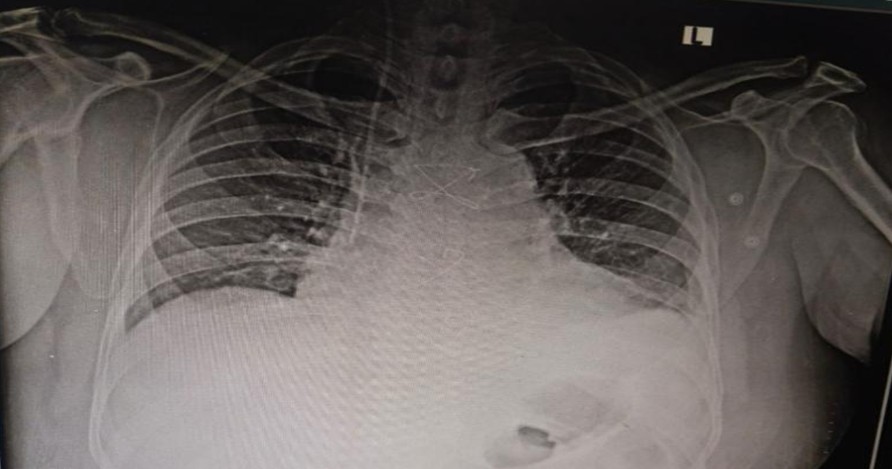

Post-operative X-ray